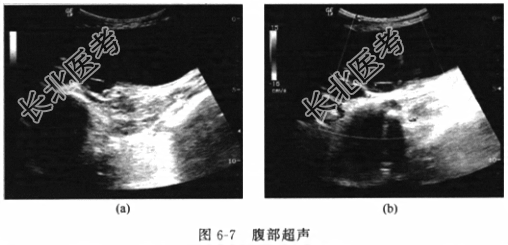

- [材料题] 患者女性,79岁,因“反复右上腹不适1个月余”入院。患者于1个月前始反复出现右上腹闷胀不适,偶伴右肩部酸胀,恶心、纳差,当时未予重视,自行口服“胆舒胶囊”,症状略有好转,但不久又出现上述不适,遂就诊于我院普外科门诊,查超声提示为“胆囊占位”,为进一步诊治住入我科。病程中无发热、黄疸、胸闷、咳嗽、腹痛、腹胀、血尿和尿频等不适。发病以来,一般情况尚可,大小便无异常。否认有手术史。体格检查体温(T)36.8℃,呼吸(R)20次/分,脉搏(P)68次/分,血压(BP)105/70mmHg。神志清楚,皮肤黏膜光滑,巩膜无黄染。腹部平坦,未见胃肠型或蠕动波,无压痛、反跳痛和肌紧张,全腹未扪及包块,叩诊呈鼓音,肠鸣音2~5次/分。直肠指检未及异常占位,退出时指套无染血。辅助检查血常规示白细胞8.9×10⁹/L,中性粒细胞88%,其他实验室检验结果包括肝肾功能、电解质、血气分析和肿瘤标志物结果未见明显异常。腹部肝胆胰脾肾超声(图6-7)提示胆囊占位,深度达肌层,尚未突破浆膜层。腹部CT(图6-8)提示胆囊底部新生物向胆囊腔内突起,直径约1cm,增强有强。